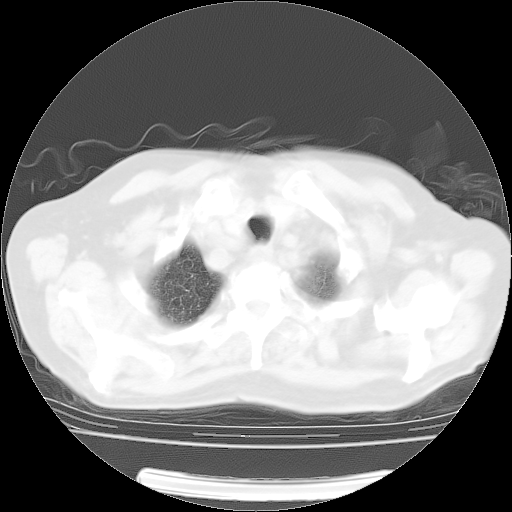

4月28日肺部CT——再次出现类似去年5月9日——透光度降低,(影像科认为)“间质性”改变。

4月28日肺部CT——再次出现类似去年5月9日——透光度降低,“间质性”改变。